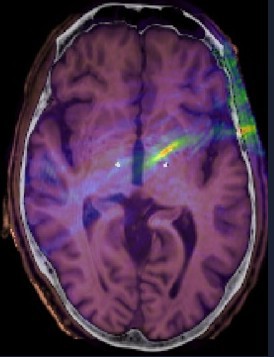

An overlay of the predicted ultrasound field (blue-red) on a two-dimensional image of the skull and brain showing the targeting accuracy of the lens.

An overlay of the predicted ultrasound field (blue-red) on a two-dimensional image of the skull and brain showing the targeting accuracy of the lens. Credit: John Eraifej.